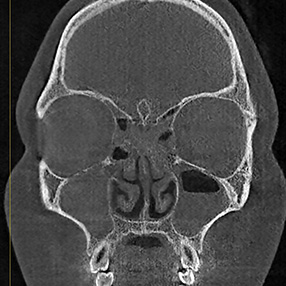

※ 축농증 수술 후 생길 수 있는 부작용으로는 출혈, 감염, 염증이 있을 수 있습니다.

본 사진은 의료기관에서 진료를 본 환자이고, 전후 사진 인물이 동일인이며,동일조건에서 촬영이 되었습니다.